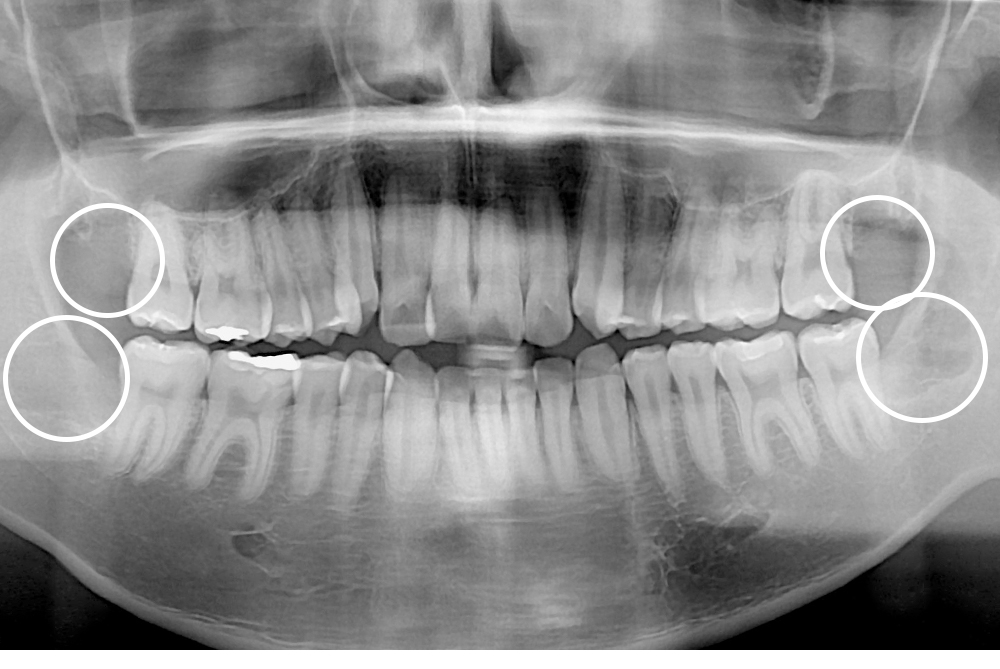

[사랑니] 매복 사랑니 발치

치료전 : 2018-02-23